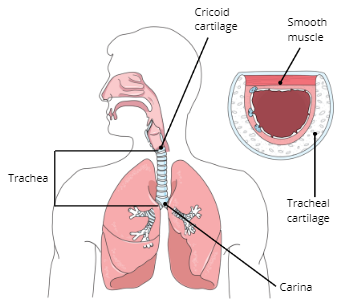

Cricoid Cartilage

Trachea

Carina

Function of Trachea